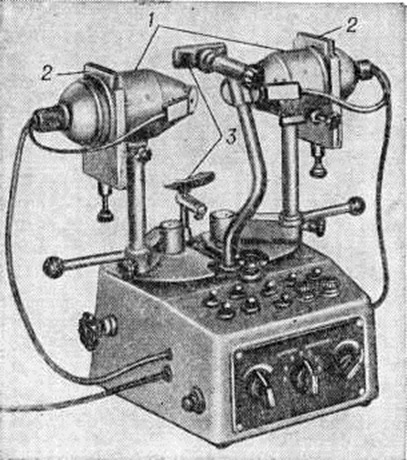

Принцип действия ортоптических приборов основан на разделении полей зрения, при котором обеспечивается одновременное предъявление раздельных физиологически равноценных тестов правому и левому глазу больного для выявления характера и степени участия каждого из глаз в бинокулярном зрении. Имеются два типа ортоптических приборов — синотипные приборы, содержащие две зрительных трубы для предъявления парных тестов, и приборы с неподвижными тестами — диплоскопы различного вида. Основными из них являются синотипные приборы; их прототипом является амблиоскоп У орта. Эти приборы применяются для определения объективного и субъективного угла косоглазия, исследования состояния мышечного баланса глаз, фузионной способности и подвижности глаз, развития фузионных резервов, выявления границ функциональный скотом, исследования состояния корреспонденции сетчатки, борьбы с аномальной корреспонденцией, развития подвижности глаз, для упражнений по стабилизации бинокулярного и стереоскопического зрения и других параметров бинокулярного зрения. Из синотипных приборов (рисунок 6) наибольшее распространение имеют синоптофор СИНФ-1 (СССР), синоптископ (Англия), синоптофор (Англия, ФРГ). Все синотипные приборы создают частично искусственные условия исследования, поскольку наличие окуляров способствует возникновению приборной аккомодации. Приборы с неподвижными тест-объектами для дали создают условия, приближенные к естественным. Однако исследования на них можно проводить только при параллельном или близком к параллельному положении зрительных осей. Небольшие отклонения от параллельности (до 10—12 призменных диоптрий) компенсируются призмами. По способу разделения полей зрения такие приборы делятся на 5 групп: механические, зеркальные, цветовые, поляроидные и растровые. К механическим приборам относятся эклипсные приборы и приборы с непрозрачными экранами-разделителями. Эклипсные приборы предназначены для поочерёдного предъявления раздельных зрительных тестов правому и левому глазу с частотой слияния мельканий. Разделение полей зрения осуществляется разделителями (обтюраторами), обеспечивающими заданную частоту мельканий. Цветовые приборы основаны на свойстве светофильтров дополнительных цветов при наложении друг на друга полностью поглощать падающий на них белый свет, а при смешении пучка света, пропускаемого ими, давать ощущение белого света. Чаще всего в качестве дополнительных применяют светофильтры красного и зелёного цветов. В СССР выпускается серийно цветотест ЦТ-1. Цветовые приборы просты по конструкции, обладают большой надёжностью, при помощи этих приборов легко обследовать детей дошкольного возраста. Поляроидные приборы отличаются от цветовых тем, что в них вместо цветных светофильтров применяются поляроидные. Отрицательной стороной поляроидных приборов является потеря со временем поляризующих свойств, особенно под воздействием теплового излучения осветителей. Растровые приборы основаны на свойстве оптических растров-решёток разделять изображения для правого и левого глаза.

Приборы для исследования и лечения двигательного аппарата глаз применяются для определения функциональный состояния глазодвигательной мышцы или групп мышц методом коордиметрии, для исследования и развития подвижности и конвергентных движений глаз, для контроля эффекта операции на глазодвигательных мышцах. Метод коордиметрии в СССР проводится с помощью прибора офтальмокоордиметра ОКМ-1 (рисунок 7). Для исследования и развития подвижности глаз предназначен прибор «Мускултренер» (СССР). Для исследования и развития конвергенции в СССР выпускается прибор под названием «Конвергенцтренер».